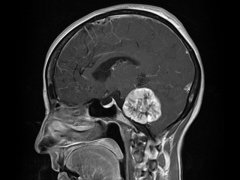

听神经瘤 ,也被称为听神经瘤,是一种生长缓慢,通常是良性的...